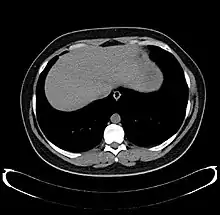

Left lobe liver tumor

The liver is a vital organ and supports almost every other organ in the body. Because of its strategic location and multidimensional functions, the liver is prone to many diseases.[52] The bare area of the liver is a site that is vulnerable to the passing of infection from the abdominal cavity to the thoracic cavity. Liver diseases may be diagnosed by liver function tests–blood tests that can identify various markers. For example, acute-phase reactants are produced by the liver in response to injury or inflammation.